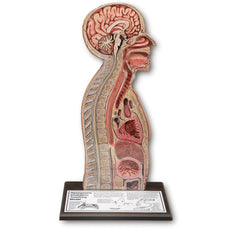

RSD’s Body Section Phantoms provide a comprehensive evaluation of the imaging system and imaging techniques under realistic conditions. They are rugged, easily transported, and shatter-proof.

RSD’s Body Sections do not replace simple geometric phantoms that are used to evaluate individual characteristics of

an imaging system. Instead, they provide comprehensive evaluation of the imaging system and imaging techniques under

realistic conditions.

Anatomy

- Bone composed of cortical (TS-1003) and trabecular bone (TS-1002) equivalent materials

- Foot encapsulated in RSD soft tissue material (TS-1001-T)

- Additional soft material made of soft tissue material with density of 1.1 g/cc